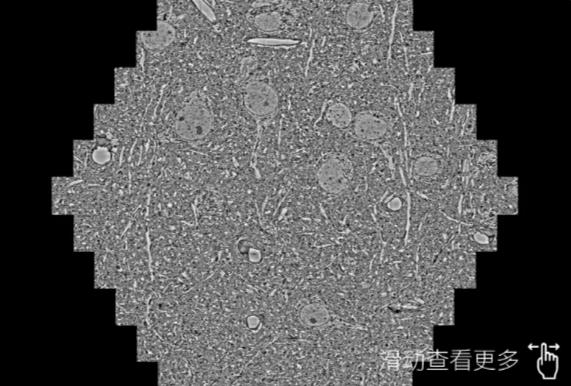

鼠脑切片。左图使用赣州蔡司赣州扫描电镜MultiSEM706对165μmx143pm面积区域成像,耗时仅需1.5秒。右图为鼠脑切片中30μm区域放大效果。样品由芝加哥大学B.Kasthuri提供。

使用蔡司高速赣州扫描电镜MultiSEM对1mm²人脑皮层组织进行高分辨成像,并对其中的各种细胞结构进行三维重构分析。左图展示了2x3mm²组织平面中锥体神经元的三维重构效果。右图显示了局部体积神经元三维重构。图像由哈佛大学chtman实验室提供,渲染图由D. Berger 制作。